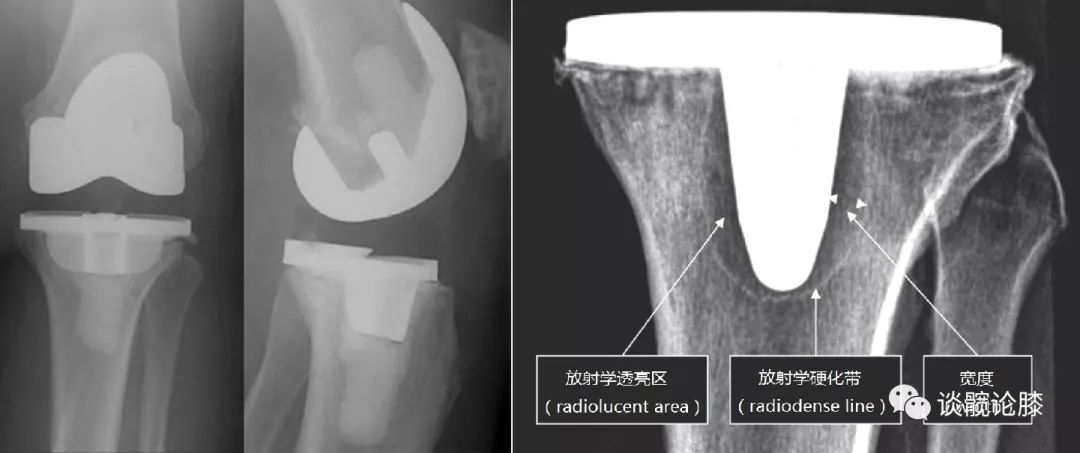

骨水泥按涂抹范围分

1、全层骨水泥技术(左图):平台下方及中心杆周围均涂抹骨水泥2、表面骨水泥技术(右图):仅在平台下方均涂抹骨水泥(研究显示:PS假体,两种疗效相似;CR假体,表面骨水泥技术松动率高)

有限元分析:表面骨水泥技术术后,胫骨近端应力遮挡小生物力学:表面骨水泥技术,术后假体稳定性较差